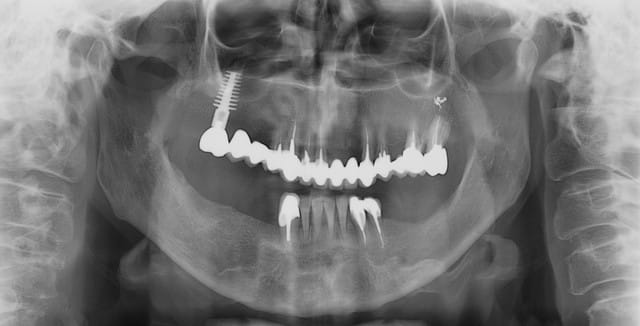

17/06/2009 à 21h12

pour ce vendredi, expansion verticale en bas à gauche, pas simple mais...

Implants à gauche...et à droite ?

Paro avancée sur 42 à 32 ??

Joli implant disk zone 16 avec bridge dent-implant.

Implants à gauche et à droite, c’est un cas d’expansion horizontale droite et gauche que je dois faire en Novembre en directe (pour des confrères Russes), et vendredi je prépare le site à gauche, pour avoir une hauteur correcte pour remplacer ensuite 35/36.37.

En principe je ne poserais pas les implants vendredi, sauf si le site est nickel pour.

Pour l’implant du haut ce n’est pas un disk, mais un D4 de Tatum (impacté) 7,5 x 4X20mm (en coupe il a une forme de D) extrême résistance et avec ce type d’implant il n’y a pas de soucis implant/dents pour les bridges.

Celui-ci doit avoir une quinzaine d’année je n’ai pas la fiche ici, si je peux je passerai le scan.

19/06/2009 à 21h39

bon ça c'est fait!